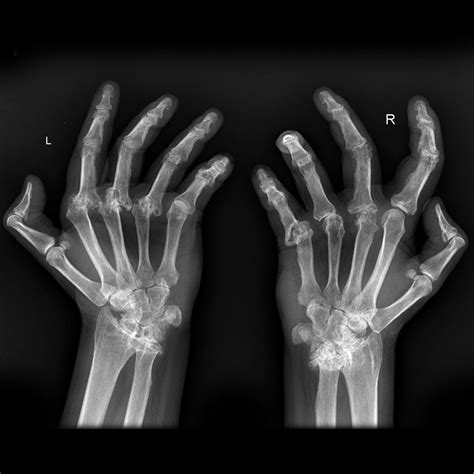

• Arthritis Assessment: Identifying the loss of joint space, bone spurs, or cartilage erosion associated with osteoarthritis or rheumatoid arthritis.

After your physician receives the report, they will schedule a follow-up appointment to discuss the results with you. Depending on what the X-ray of hand reveals, your treatment plan could range from a simple splint or cast for a minor fracture to physical therapy for overuse injuries, or medication management for chronic arthritic conditions.

• Track the progression of degenerative diseases to adjust treatments accordingly.